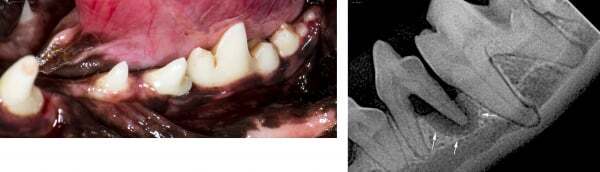

육안으로는 크게 문제가 없는것처럼 보이지만 실제로는 문제가 심각한 증례 사진 서베이 from google image